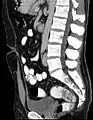

CT scan (sagittal reconstruction) showing an urachus rest as an incidental finding in a 44-year-old man, the trajectory moves forward and upward from the bladder to the umbilicus in the midline.